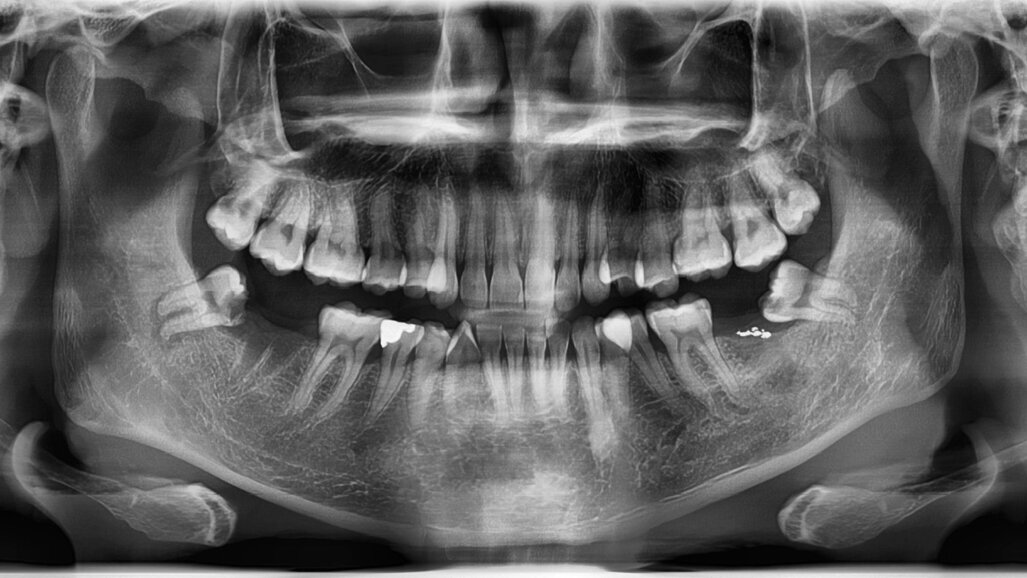

Demirjianove faze formiranja zuba ocjenjuju se s pomoću panoramskih rendgenskih snimki, a pravilno pozicioniranje pacijenta ključno je za snimanje kvalitetnih slika. Ove rendgenske snimke omogućuju stomatolozima da klasificiraju razvojni stupanj trećeg kutnjaka koristeći se referentnim skupovima podataka za procjenu kronološke dobi. Posebno treba istaknuti stadije G i H. U stadiju G, vrhovi korijena ostaju otvoreni, dok se u stadiju H zatvaraju, označavajući potpunu formaciju zuba. Dok čimbenici poput spola, etničke pripadnosti i genetike utječu na formiranje zuba, okolišni stres obično ima minimalan učinak, ali prehrana, epizode visoke temperature i određeni lijekovi mogu utjecati na morfogenezu zuba.

Istraživači sa Sveučilišta Malmö i Švedske agencije za procjenu zdravstvene tehnologije i socijalnih usluga nastojali su istražiti korelaciju između potpuno zrelog trećeg kutnjaka u donjoj čeljusti prema Demirjianovoj metodi i kronološke dobi. Ključno pitanje bila je pouzdanost primjene Demirjianova stupnja H za određivanje je li netko navršio 18 godina.

Pregled je uključivao petnaest istraživanja koja su obuhvatila trinaest zemalja i uključivala sudionike u dobi od tri do 27 godina. Nalazi su naglasili da je u dobi od osamnaest godina udio pojedinaca s donjim trećim kutnjakom u stadiju H bio u rasponu od 0 % do 22 % za muškarce i 0 % do 16 % za žene. Pregled nije mogao definitivno povezati Demirjianov razvoj stupnja H trećeg kutnjaka u donjoj čeljusti s kronološkom dobi, što ukazuje na to da je nepouzdano primjenjivati ovu metodu za određivanje je li netko mlađi ili stariji od 18 godina. Klinički je utvrđeno da se stope razvoja trećeg kutnjaka razlikuju između populacije, a njihova je prisutnost nedosljedna zbog kongenitalne odsutnosti ili drugih stomatoloških problema.